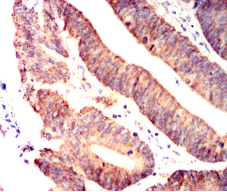

IHC    1/200 - 1/1000